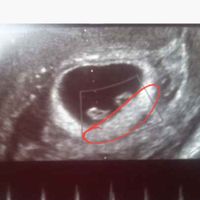

Hola! Quería preguntaros si entendéis el método Ramzi si sabéis que puede ser. Os lo agradecería muchísimo. Es una ecografía de 7 semanas